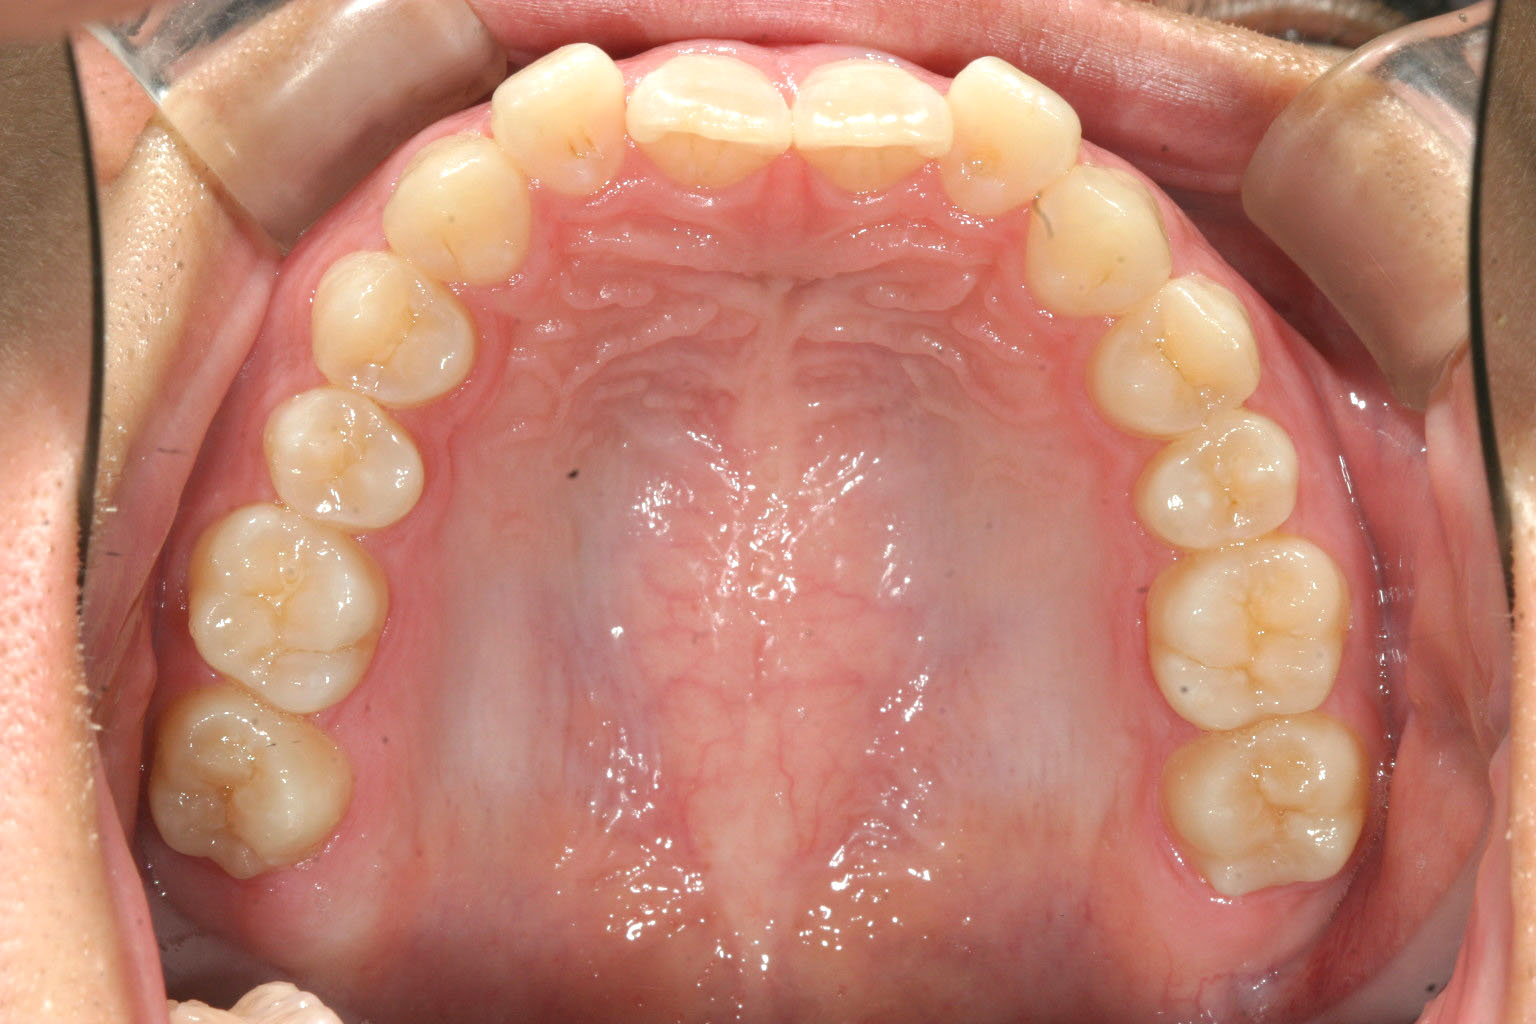

前歯が完全に内向いて萌えているのが分かります。

上顎が綺麗に並びました。